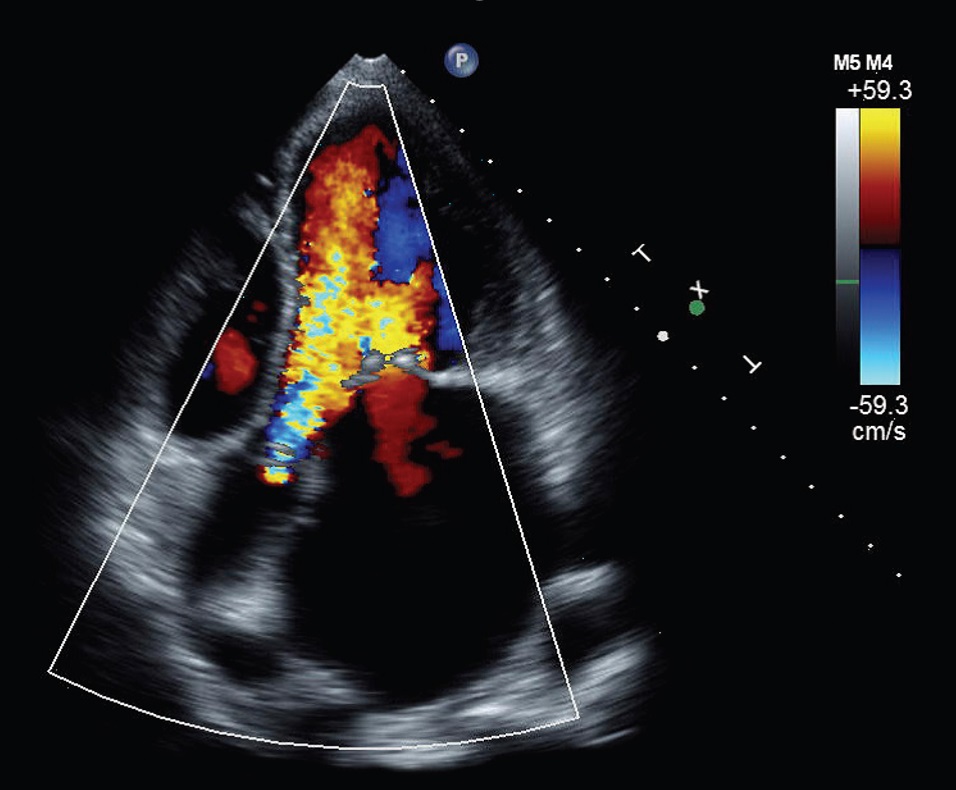

Hình ảnh trong buồng tim trên siêu âm Doppler màu

Trong quá trình làm siêu âm tim, bác sỹ sẽ dùng một hoặc một số đầu dò thích hợp để soi vào tim qua thành ngực hoặc từ vị trí khác để

lấy hình ảnh của tim thông qua sóng siêu âm.

- Các van tim hoạt động bình thường hay không

Siêu âm tim cho thấy hình ảnh, kích thước van tim cũng như hoạt động của van tim trong các chu kỳ bơm - đẩy máu,

cách thức hoạt động của van tim, có vôi hóa hay các bất thường khác tại van tim hay không. Bình thường có 4 van tim là:

van động mạch chủ, van động mạch phổi, van hai lá và van ba lá

- Van tim có bị hẹp hay không

Đánh giá các lỗ van tim có bị hẹp so với diện tích van bình thường làm cho dòng máu qua van bị khó khán hay không

- Có bị hở van tim hay không

Kiểm tra xem lá của các van tim có đóng kín hay không. Trong một số trường hợp, van tim có thể bị hở làm

trào ngược dòng máu theo chiều ngược với chiều dòng máu lưu thông bình thường trong tim